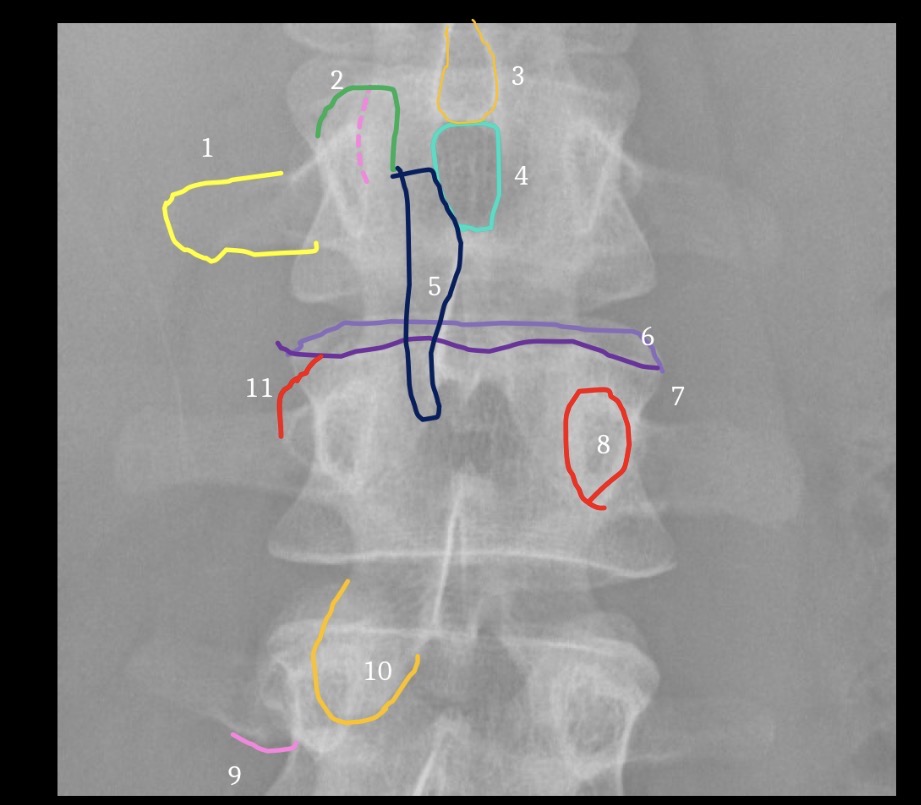

1

Inferior Margin of right 1th rib

2

Spinous process of T12

3

Left pedicle of L2

4

Left transverse process of L3

5

Right facet joint space L2-3

6

L4 spinous process

7

Inferior margin of right lamina L5

8

Right sacral ala

9

Superior margin right 1st anteror sacral foramen

10

Left margin of sacrum

11

Left iliac crest